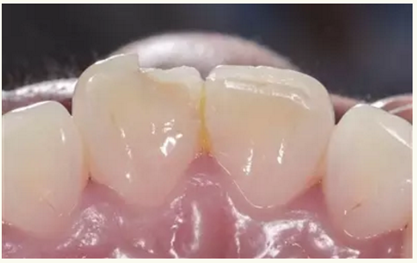

▲術(shù)前(舌側(cè))

▲術(shù)后即刻(唇側(cè))

▲術(shù)后即刻(舌側(cè))